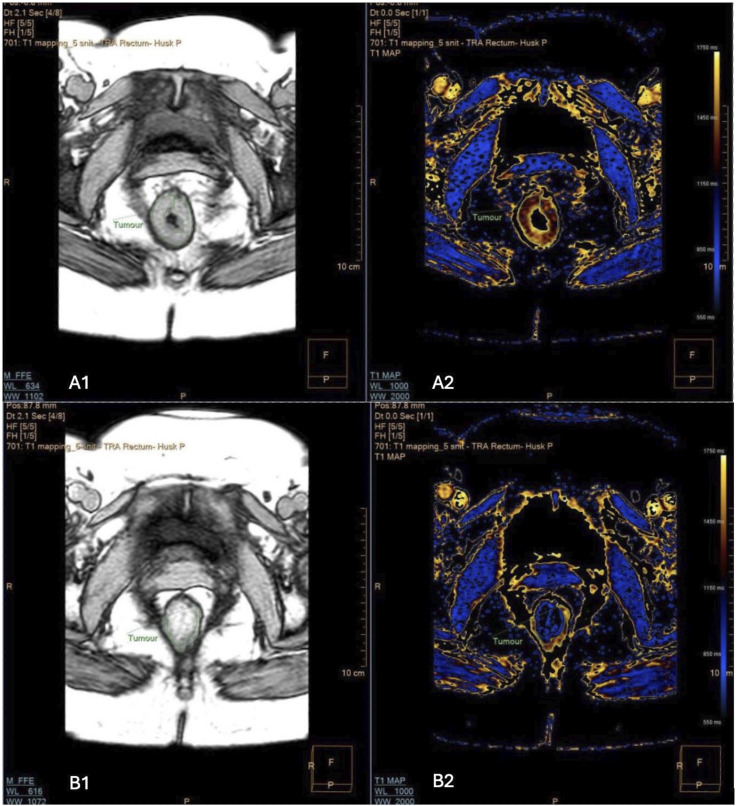

Material and methods: MRI scans are conducted on a 1.5 T MRI-unit. T1RT is measured at time of diagnosis and 6 weeks after neoadjuvant treatment. Experienced radiologists analyse T1RT using specialised software. Treatment decisions are made in multidisciplinary team conferences based on tumour staging. Endpoints include tumour visibility on MRI and endoscopy, along with histopathological analysis of surgical specimens. Statistical methods include t test and receiver operating characteristic curves. Sample size calculations showed we must enrol 76 participants to achieve a statistical power of 80% with an α = 0.05.

Conclusion: The implications of this study extend to the potential refinement of treatment strategies, offering patients the prospect of improved outcomes and the potential avoidance of surgery-associated risks. We expect to find a lower relaxation time in fibrotic tissue compared to non-responsive cancerous tissue after 6 weeks.